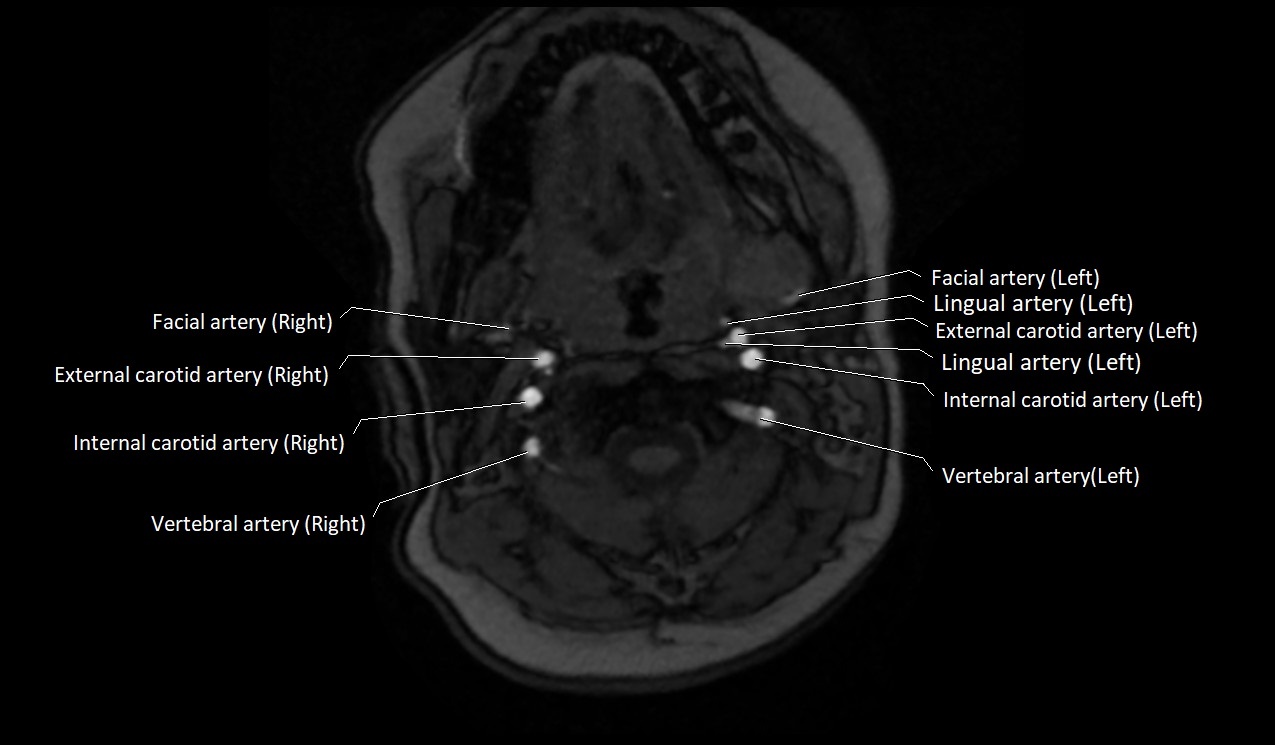

MRI images

image